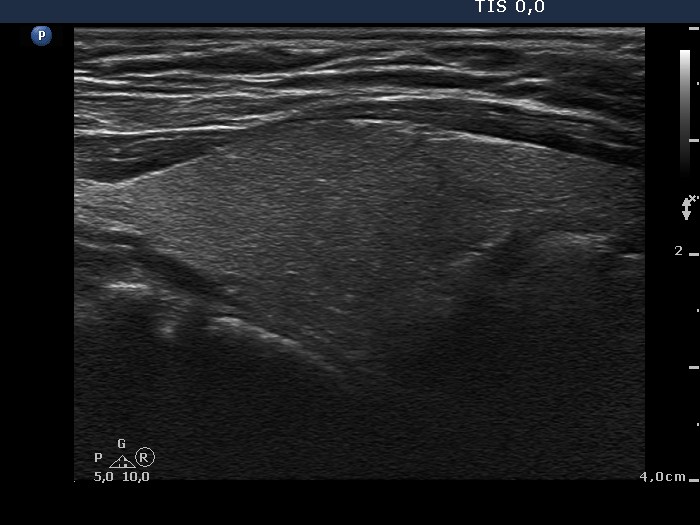

Oxyphilic adenoma - Case 11. (ultrasonographic picture 2)

Right lobe, longitudinal scan. Note the central protrusion of the lobe which caused nodular appearance on palpation.